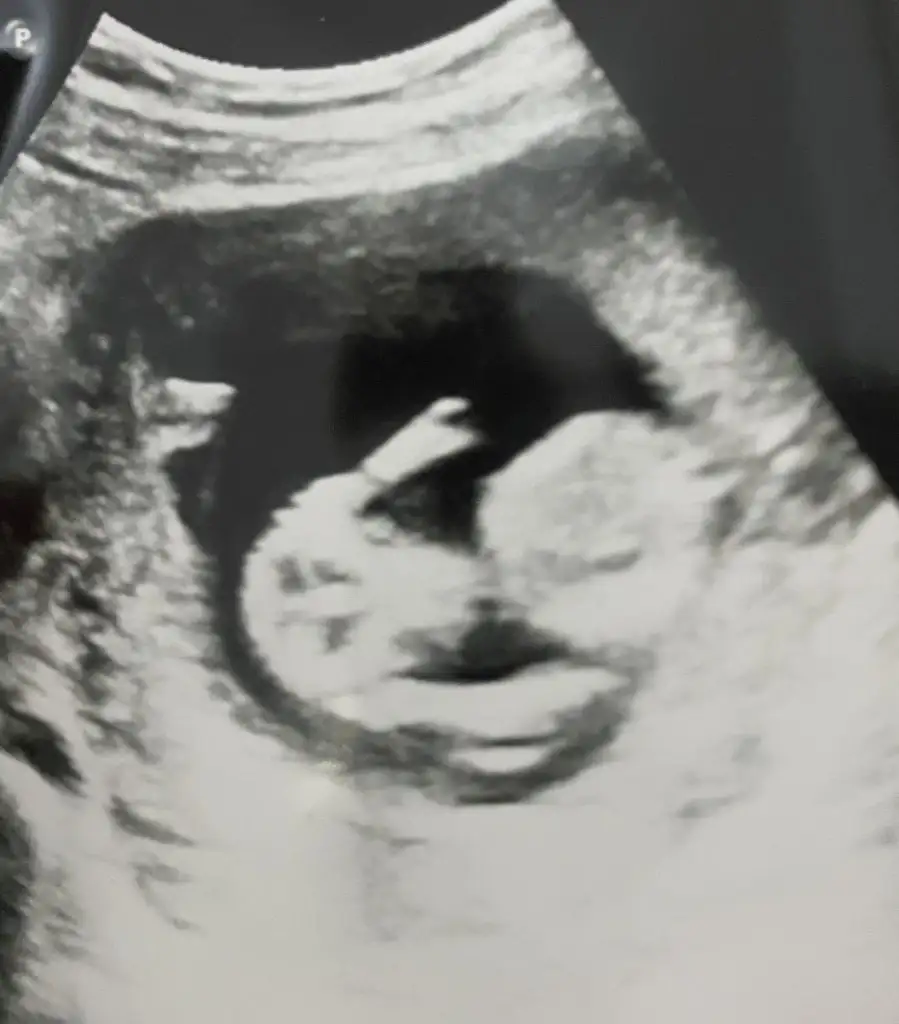

Canım bu fotoğrafada bakar mısın peki 2 çıkıntı ne kusura bakma seni de yoruyorumCanım sanki kız gibi

Evet işte merak ediyor insan yoğun duygularla aşkın da erkek kız farkedeceğinden değil ama ah merakBen 14 haftaligim daha ben bile bilmiyorum cinsiyeti kuzum doktorlar söylemiyor 12 hafta çok erken daha yanılma payı çok yüksek 16 hafta doldurunca en net belli oluyor

Aynen öyle . Çok sevindim Rabbim gönlünüze göre vermiştir inşallahEvet işte merak ediyor insan yoğun duygularla aşkın da erkek kız farkedeceğinden değil ama ah merak17 haftamızdayız belli oldu teşekkürler

Kız bnce siznKızlar banada bakar mısınız

Bende erkek diyorumMerhaba hanımlar tabiki her şeyin başı sağlık ama her anne gibi merakla beklemek çok heyecanlı ve sabır gerektiren bir durum sadece merak 12 haftalık gebeyim dr hiç bir cinsiyet tahmininde bulunmuyor eee ben de merakımdan sizlere tahmin sormak istedimEki Görüntüle 3405813